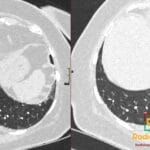

- Radiology Cases: Images with a to-the-point discussion highlighting the specific diagnostic criteria.

Latest Radiology Cases